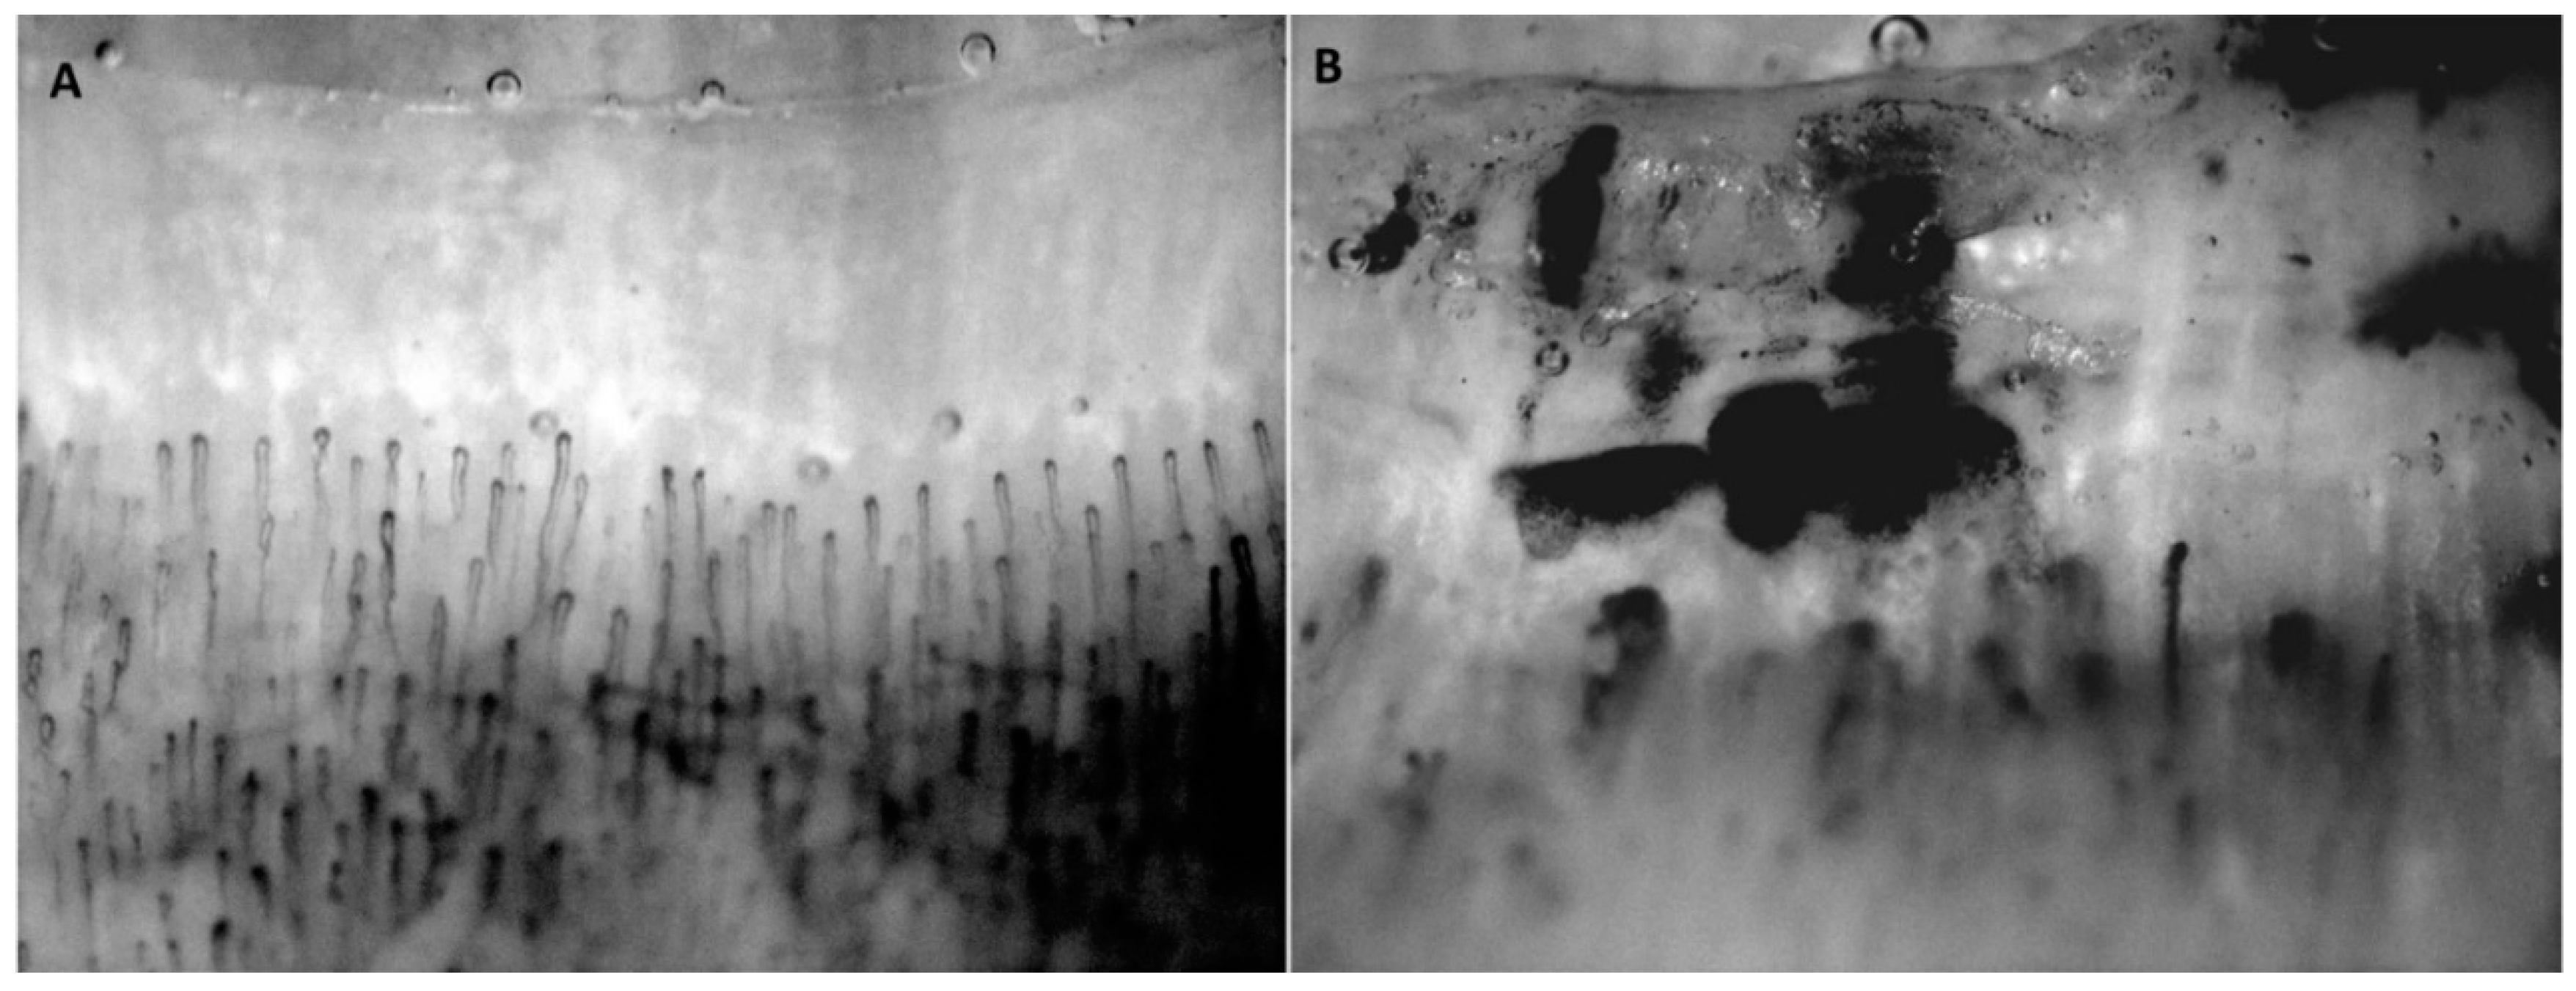

- Caramaschi, P.; Volpe, A.; Canestrini, S.; Bambara, L.M.; Faccini, G.; Carletto, A.; Biasi, D. Correlation between homocysteine plasma levels and nailfold videocapillaroscopic patterns in systemic sclerosis. Clin. Rheumatol. 2007, 26, 902–907. [Google Scholar] [CrossRef]

- Cutolo, M.; Pizzorni, C.; Tuccio, M.; Burroni, A.; Craviotto, C.; Basso, M.; Seriolo, B.; Sulli, A. Nailfold videocapillaroscopic patterns and serum autoantibodies in systemic sclerosis. Rheumatology 2004, 43, 719–726. [Google Scholar] [CrossRef]